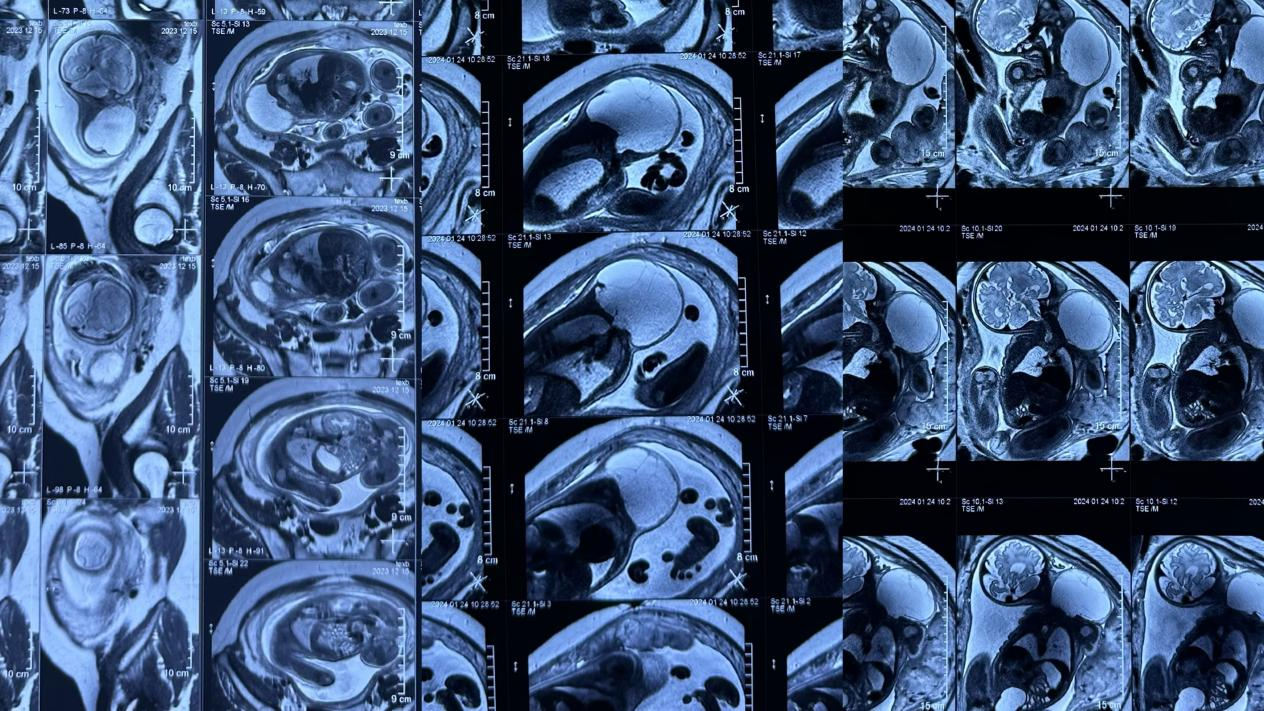

胎儿淋巴管畸形磁共振检查

儿童淋巴管畸形磁共振检查

【辅助检查】1、超声检查提示无回声区,有分隔,呈囊状改变,CDFI:无血流信号,2、磁共振检查提示长T1长T2信号,囊状改变,压脂序列呈高信号,增强无明显强化。目的:1、超声检查用于明确诊断,2,磁共振检查用于了解淋巴管畸形病灶范围、侵及周围组织情况以及是否包绕重要器官如血管神经以及气管等。